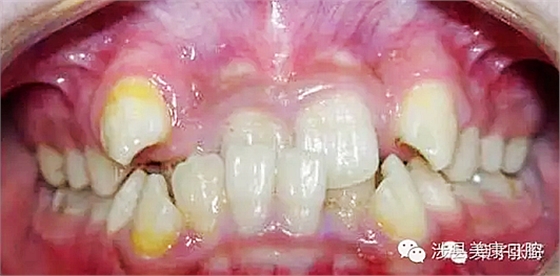

影響乳牙下方的恒牙胚。

造成恒牙釉質(zhì)發(fā)育不良。

![%ZE{HJY7[$E@]P[}W0CMW~4.png %ZE{HJY7[$E@]P[}W0CMW~4.png](/Mobile/UploadFiles/FCK/2017-04/6362664370621357178946990.png_280.jpg)

引起恒牙萌出亂位。

引起牙齦發(fā)炎。